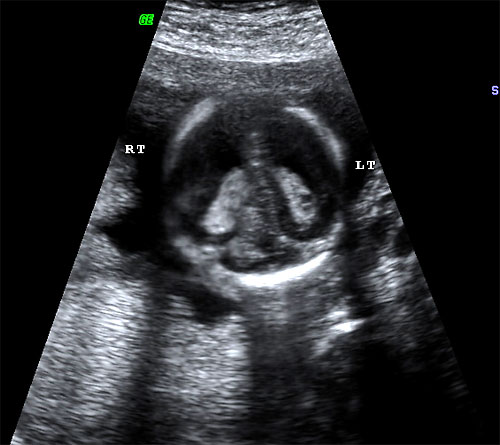

- Echogenic intracardiac foci

- Detection of Aneuploidy: "Soft Signs"

- All are more prevalent in aneuploid fetus